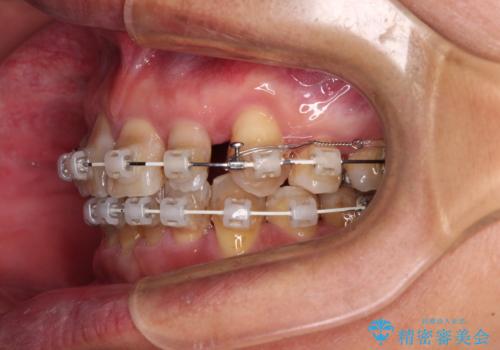

- 矯正装置

- 審美装置

- 骨格的な咬み合わせのズレ、前歯のデコボコとクロスバイトを気にして来院された患者様です。

全額的にデコボコが強いため、上下左右の小臼歯計4歯を抜歯し、ワイヤー装置による矯正治療を行うこととしました。

抜歯する歯の一部をセオリーである第一小臼歯ではなく、第二小臼歯にすることで、骨格的なずれをカバーするように計画しました。